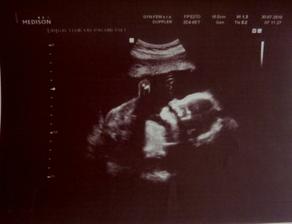

14. 6. 2010 - Dneska jsem s velkými obavami, ale i nadějemi šla na prvotrimestrální screening. Pan doktror naše mimi vyhodnotil jako krásné🙂. NT hodnotu naměřil 1,9, změřil tepovou frekvenci, ukázal, že miminku nic nechybí. Měří 7,5 cm. Výsledky krve budou za týden, ale i tak jsem moc šťastná. Byla jsem tak vyplašená, že jsem si neřekla o fotku, takže svůj druhý trimestr začínám fotkou rostoucího bříška.

Pěkné bříško 🙂 a krásné NT!